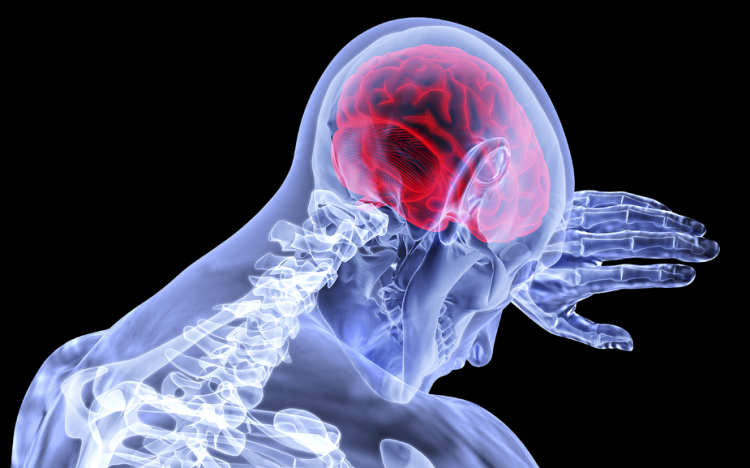

Néhány hónapon belül kiderülhet, hogy érinti-e a fertőzés az agyat

Néhány hónapon belül kiderülhet, hogy a koronavírus-fertőzés érinti-e az agyat, és ha igen, mely területeit - mondta Dénes Ádám, a Kísérleti Orvostudományi Kutatóintézet (KOKI) munkatársa az M1 csatornán csütörtök este.

A kutatásban részt vevő Dénes Ádám elmondta: pár hónap alatt választ kaphatnak a kérdésre, hogy a koronavírussal fertőződött betegek agyszövetében jelen van-e a vírus, ha igen, mely agyterületeken, illetve, hogy a vírus fertőzheti-e például az idegsejteket.

Hozzátette: azt is rövid idő alatt fel lehet térképezni, hogy a fertőzöttek agyában milyen gyulladásos faktorok vannak jelen és milyen mennyiségben.

Dénes Ádám kiemelte: ezen ismeretek birtokában választ lehetne adni arra, hogy az antivirális szernek be kellene-e jutni az agyba, vagy hogy vannak-e olyan eljárások, amelyekkel a neurológiai tünetek mérséklésével lehetne javítani a betegek általános állapotán.

"Ha tisztán látnánk, hogy súlyos esetekben milyen mértékű az agyi érintettség (.), akkor sok olyan terápiás gondolatot lehetne egy tapasztalt klinikusnak javasolni, amely a betegek állapotán akár rögtön javíthatna" - mondta a kutató.

Megjegyezte: jelenleg az orvosok "próba-szerencse alapon" igyekeznek segíteni a betegeken, mivel a koronavírus-fertőzésben elhunytak boncolását nagyon kevés helyen engedélyezik a világon, így adat is kevés van arról, hogy a súlyos esetekben milyen mértékű az idegrendszer érintettsége.

Dénes Tamás az agy lehetséges érintettségéről szólva kiemelte: gyulladásos folyamatok és lokális fertőzés is hathat az agyra.

Kifejtette: hosszan tartó fertőzés esetén, még ha az lokalizált is, például a tüdőben, "rendkívül sok gyulladásos faktor szabadul el a keringésben és ezek előbb utóbb elérik az agyat is".

Példaként említette, hogy influenzás megbetegedés esetén több tünet, mint a levertség vagy a szapora szívverés annak következménye, hogy a "gyulladásos faktorok elérik az agy különböző területeit, és ott változásokat okoznak".

A koronavírusos megbetegedés esetén tehát a felfokozott gyulladás nemcsak a perifériás szervek keringésére hat, hanem nagyon komolyan befolyásolhatja az agyi légzőközpont vagy más agyi központ működését, így okozva még súlyosabb tüneteket. Ehhez pedig nem is kell, hogy a vírus bejusson az agyba.

A másik kérdés, hogy a "fertőző ágens ezenfelül is jelen lehet az agyszövetben, és ott külön gyulladást okozhat, illetve befolyásolhatja ezeken a területeken az idegsejtek működését". Erre más, járványt nem okozó koronavírusok, mint a SARS és a MERS vírus esetében van is bizonyíték - mondta a kutató.